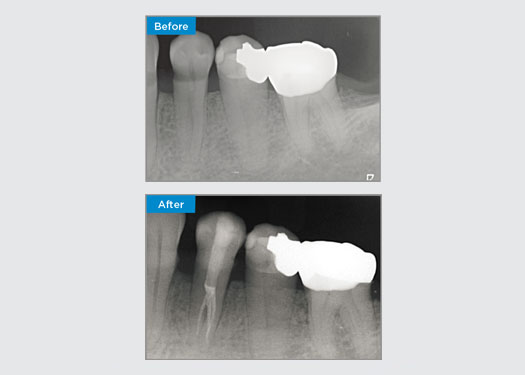

The patient was presented with irreversible pulpitis on tooth 46. From the pre-op radiograph, tooth 46 is presented with an additional distal root (Radix Entromolaris tooth morphology). A CBCT scan has confirmed the presence of DL root with severe root curvature. A careful file selection is critical for this delicate DB root.

Dr Jack Lin, Endodontist, Sydney, NSW Australia

In this situation, tooth/root structure preservation is essential to reduce the risk of ledging, transportation, zipping, perforation, and root fracture. Case selection, diagnosis, and pre-treatment planning are important. Endodontic file selection with flexibility, efficiency, and respect of natural root anatomy is critical.